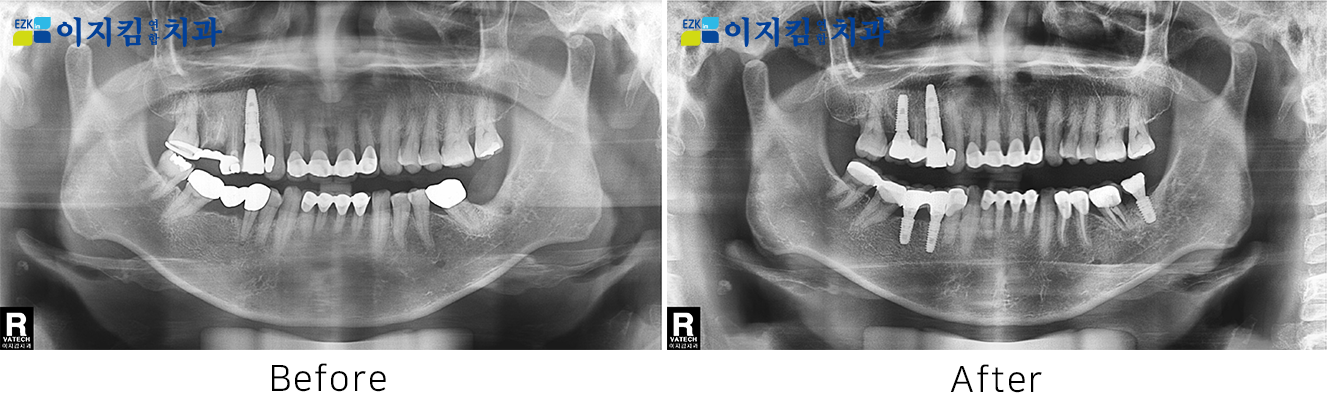

ÀÓÇöõÆ® Àü ¡¤ ÈÄ »çÁø